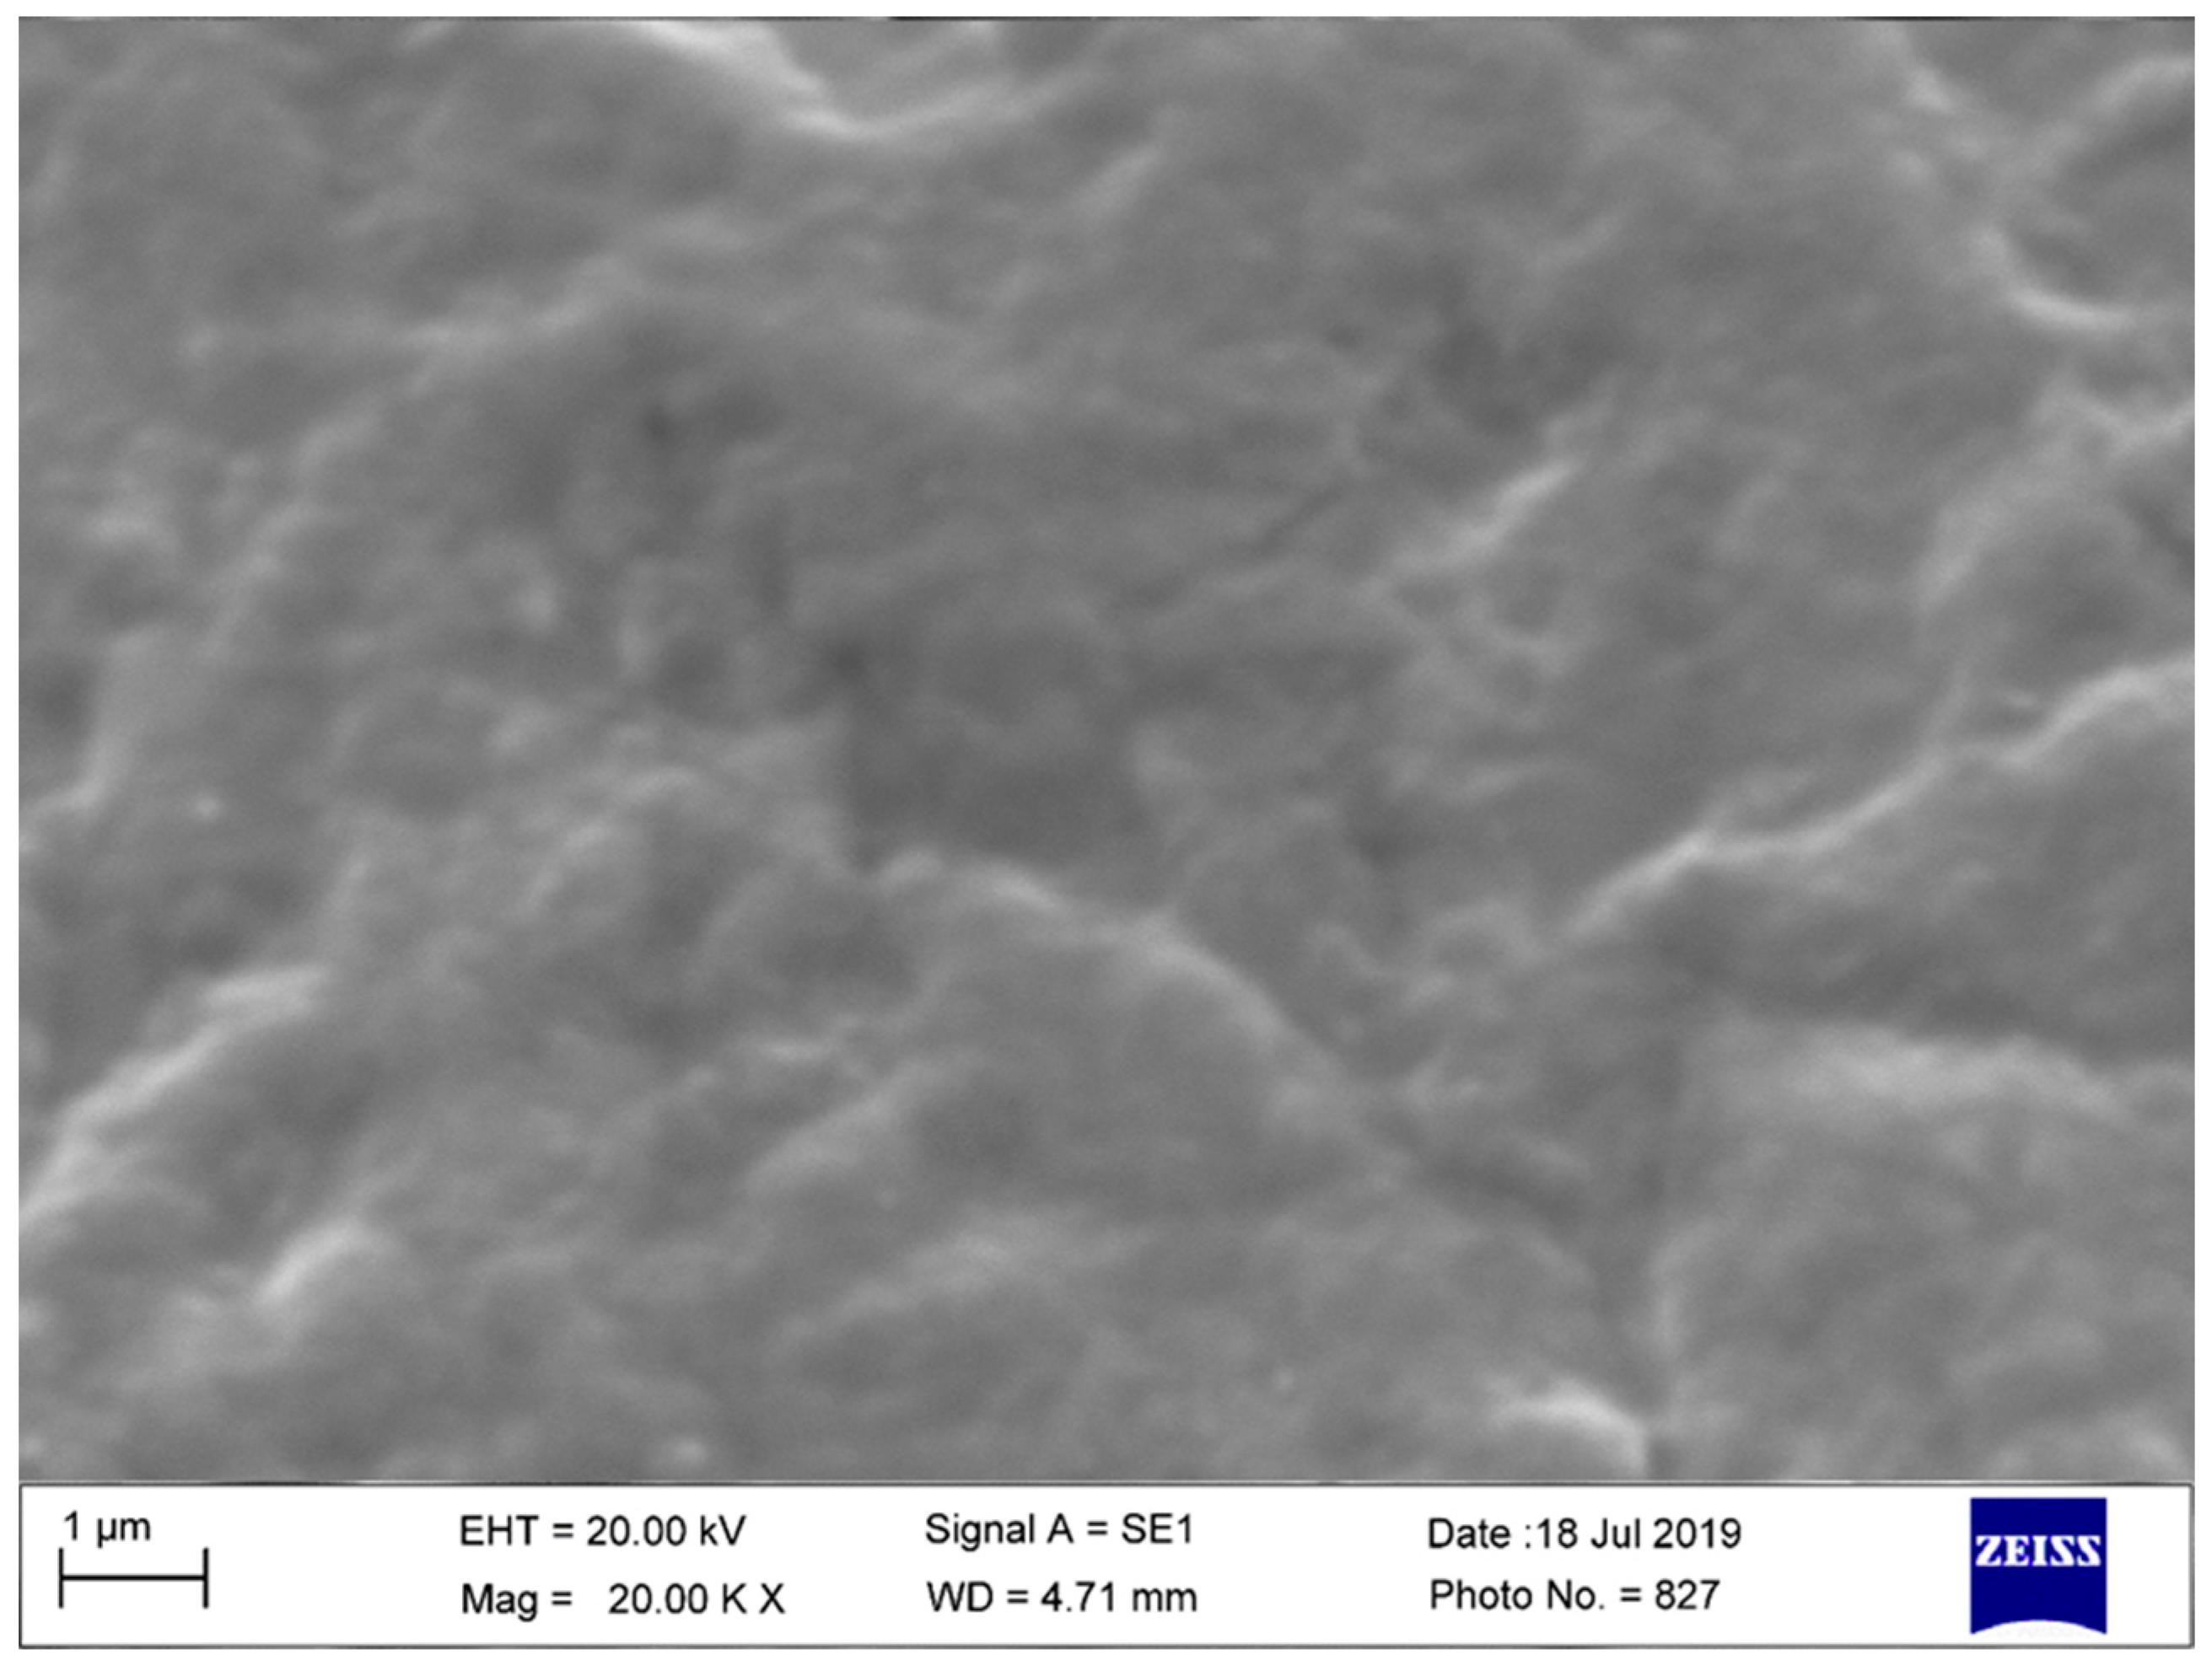

3.2. Scanning Electron Microscopy-EDS Analysis

3.2.2. Used and Sterilized Drill and Conical Tapper